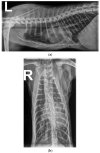

A five-month-old, 3.8 kg intact male Maine coon cat presented for dyspnea characterized by increased respiratory effort in addition to open-mouth breathing. Thoracic radiographs showed pectus excavatum, enlarged cardiac silhouette, and generalized interstitial patterns. Echocardiography revealed normal left atrial (LA) and left ventricular dimensions. A large tubular structure, suspected to be a distended pulmonary vein (PV), was identified as draining into the LA. Severe eccentric and concentric right ventricular hypertrophy and paradoxical septal motion were noted. Based on Doppler echocardiography, both pulmonary venous and pulmonary artery pressure was severely elevated. Clinical, radiographic, and echocardiographic abnormalities were hypothesized to result from pulmonary vein stenosis (PVS), causing severely elevated pulmonary venous pressures and resulting in clinical signs of left-sided congestive heart failure (L-CHF) and severe post-capillary pulmonary hypertension (Pc-PH). The prognosis for good quality of life was assessed as poor, and the owner elected euthanasia. Necropsy confirmed the presence of PVS with severe dilation of the PVs draining all but the left cranial lung lobe. All lung lobes except the left cranial lobe had increased tissue density and a mottled cut surface. This case report shows that, in rare cases, both L-CHF and Pc-PH may be present without LA enlargement. To the authors' knowledge, this is the first report on PVS in veterinary medicine.